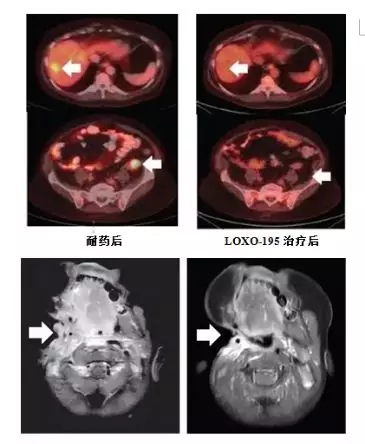

尽管,当前已经有一些参与拉罗替尼临床试验的患者出现了耐药。但可喜的是,依据拉罗替尼的耐药机制,第二代TRK靶向药物LOXO-195已经被FDA批准正式开展临床试验,专门来对抗耐药新突变,且已在部分耐药患者的治疗中取得了较好成效,具体如下: